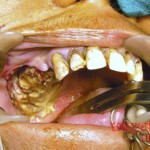

During examination, doctors found an extensive area of dead tissue in the right upper jaw. The damage extended from the canine tooth backward beyond the last part of the jaw, toward the midline of the palate and into the gum area. The surrounding mucosa appeared relatively normal at first glance, which was deceptive. On palpation, the maxillary sinus area was also painful, and signs of inflammation and a small amount of pus were present in the right nasal cavity.